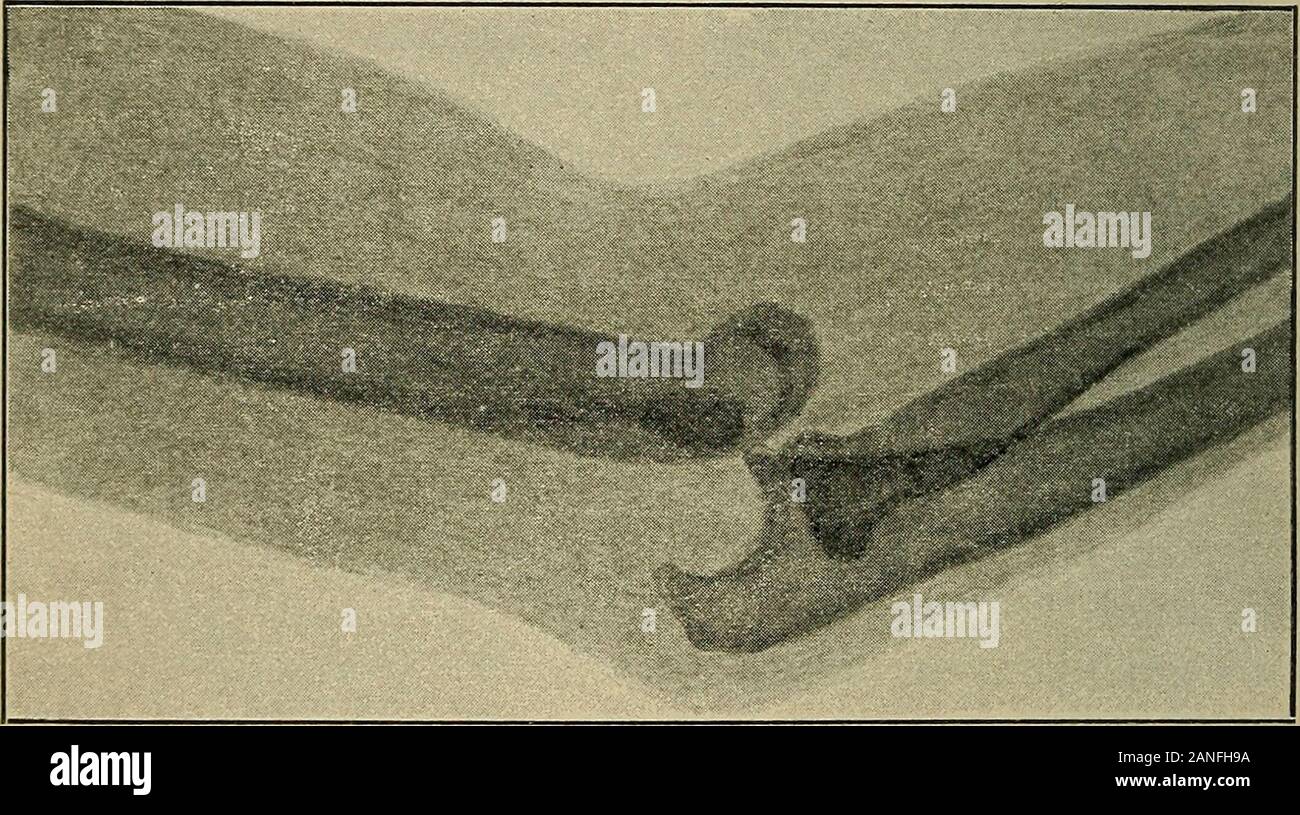

Atlas and epitome of traumatic fractures and dislocations . Fig. 81.—Eecent backward dislo-cation of the left forearm in a boyfourteen years of age (Kriiger, 1896).Swelling, prominence of the olecra-non, shortening of the forearm areseen. The dislocation was reducedand perfect recovery ensued. 188 FRACTURES AND DISLOCATIONS. cadaver. The arm need only be overextended to producea tear in the anterior segment of the articular capsule ; theolecranon during this movement is braced against the pos-terior supratrochlear fossa, and after the bones have beensufficiently forced apart, the forearm is su Stock Photohttps://www.alamy.com/image-license-details/?v=1https://www.alamy.com/atlas-and-epitome-of-traumatic-fractures-and-dislocations-fig-81eecent-backward-dislo-cation-of-the-left-forearm-in-a-boyfourteen-years-of-age-kriiger-1896swelling-prominence-of-the-olecra-non-shortening-of-the-forearm-areseen-the-dislocation-was-reducedand-perfect-recovery-ensued-188-fractures-and-dislocations-cadaver-the-arm-need-only-be-overextended-to-producea-tear-in-the-anterior-segment-of-the-articular-capsule-theolecranon-during-this-movement-is-braced-against-the-pos-terior-supratrochlear-fossa-and-after-the-bones-have-beensufficiently-forced-apart-the-forearm-is-su-image340247638.html

Atlas and epitome of traumatic fractures and dislocations . Fig. 81.—Eecent backward dislo-cation of the left forearm in a boyfourteen years of age (Kriiger, 1896).Swelling, prominence of the olecra-non, shortening of the forearm areseen. The dislocation was reducedand perfect recovery ensued. 188 FRACTURES AND DISLOCATIONS. cadaver. The arm need only be overextended to producea tear in the anterior segment of the articular capsule ; theolecranon during this movement is braced against the pos-terior supratrochlear fossa, and after the bones have beensufficiently forced apart, the forearm is su Stock Photohttps://www.alamy.com/image-license-details/?v=1https://www.alamy.com/atlas-and-epitome-of-traumatic-fractures-and-dislocations-fig-81eecent-backward-dislo-cation-of-the-left-forearm-in-a-boyfourteen-years-of-age-kriiger-1896swelling-prominence-of-the-olecra-non-shortening-of-the-forearm-areseen-the-dislocation-was-reducedand-perfect-recovery-ensued-188-fractures-and-dislocations-cadaver-the-arm-need-only-be-overextended-to-producea-tear-in-the-anterior-segment-of-the-articular-capsule-theolecranon-during-this-movement-is-braced-against-the-pos-terior-supratrochlear-fossa-and-after-the-bones-have-beensufficiently-forced-apart-the-forearm-is-su-image340247638.htmlRM2ANFH9A–Atlas and epitome of traumatic fractures and dislocations . Fig. 81.—Eecent backward dislo-cation of the left forearm in a boyfourteen years of age (Kriiger, 1896).Swelling, prominence of the olecra-non, shortening of the forearm areseen. The dislocation was reducedand perfect recovery ensued. 188 FRACTURES AND DISLOCATIONS. cadaver. The arm need only be overextended to producea tear in the anterior segment of the articular capsule ; theolecranon during this movement is braced against the pos-terior supratrochlear fossa, and after the bones have beensufficiently forced apart, the forearm is su